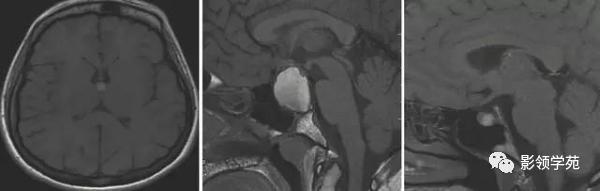

图 3 左图为四叠体池的脂肪瘤;右图为右侧颞叶的皮质层状坏死(皮质层状坏死可以发生在皮层也可以发生在深部灰质)

图 4 左图位于 Monro 孔胶样囊肿;中图为位于蝶鞍上颅咽管瘤;右图为 Rathke’s 裂囊肿